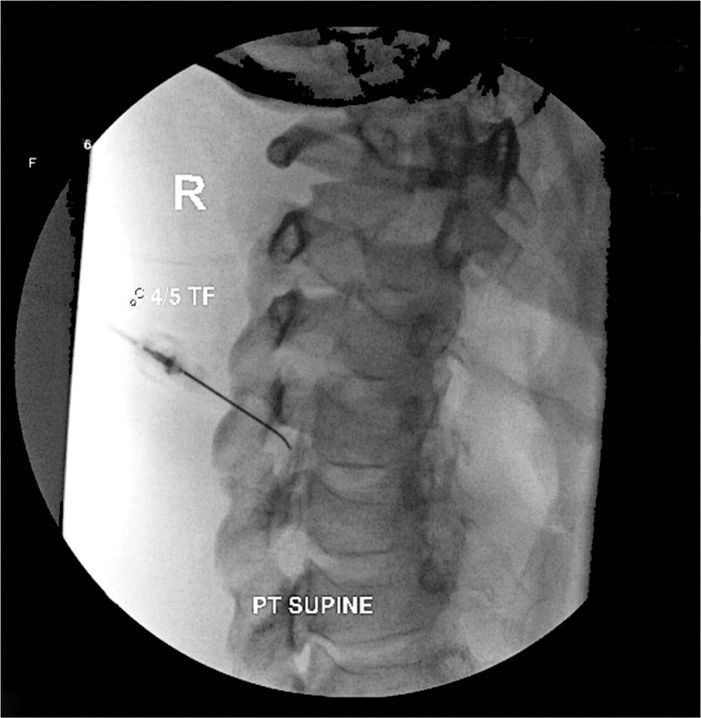

Dorsal Root Ganglion Block / Transforaminal Epidural.

Dorsal Root Ganglion Block. The diagnostic nerve root blocks were performed twice, with pain reduction of 50% defined as a positive block. Selective dorsal root ganglion blocks (drgbs) have been used in these situations to aid the diagnostic process, although their use remains controversial.

A c2 dorsal root ganglion block is an injection performed on the cervical spine (neck area). Drg stimulation is a technology that uses electricity to block pain signals. All blocks were performed as described by the spine.

This ganglion contains nerves that carry sensation. Dorsal root ganglion blocks (nerve root injections) are a procedure in which the spinal nerve roots are injected with local anaesthetic and steroid to treat pain caused by irritation and. The sensory nerves enter through a hole referred to as the intervertebral foramen.